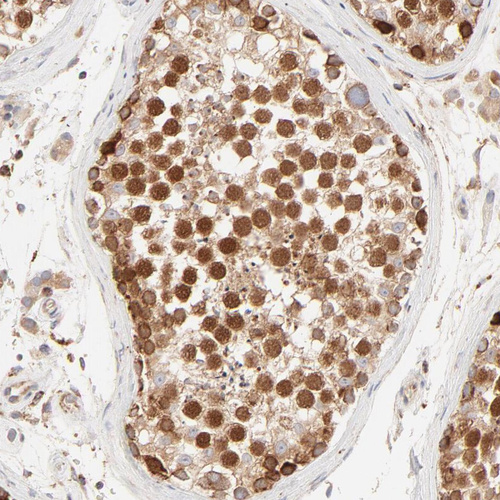

Immunohistochemical staining of human duodenum shows strong cytoplasmic positivity in glandular cells.